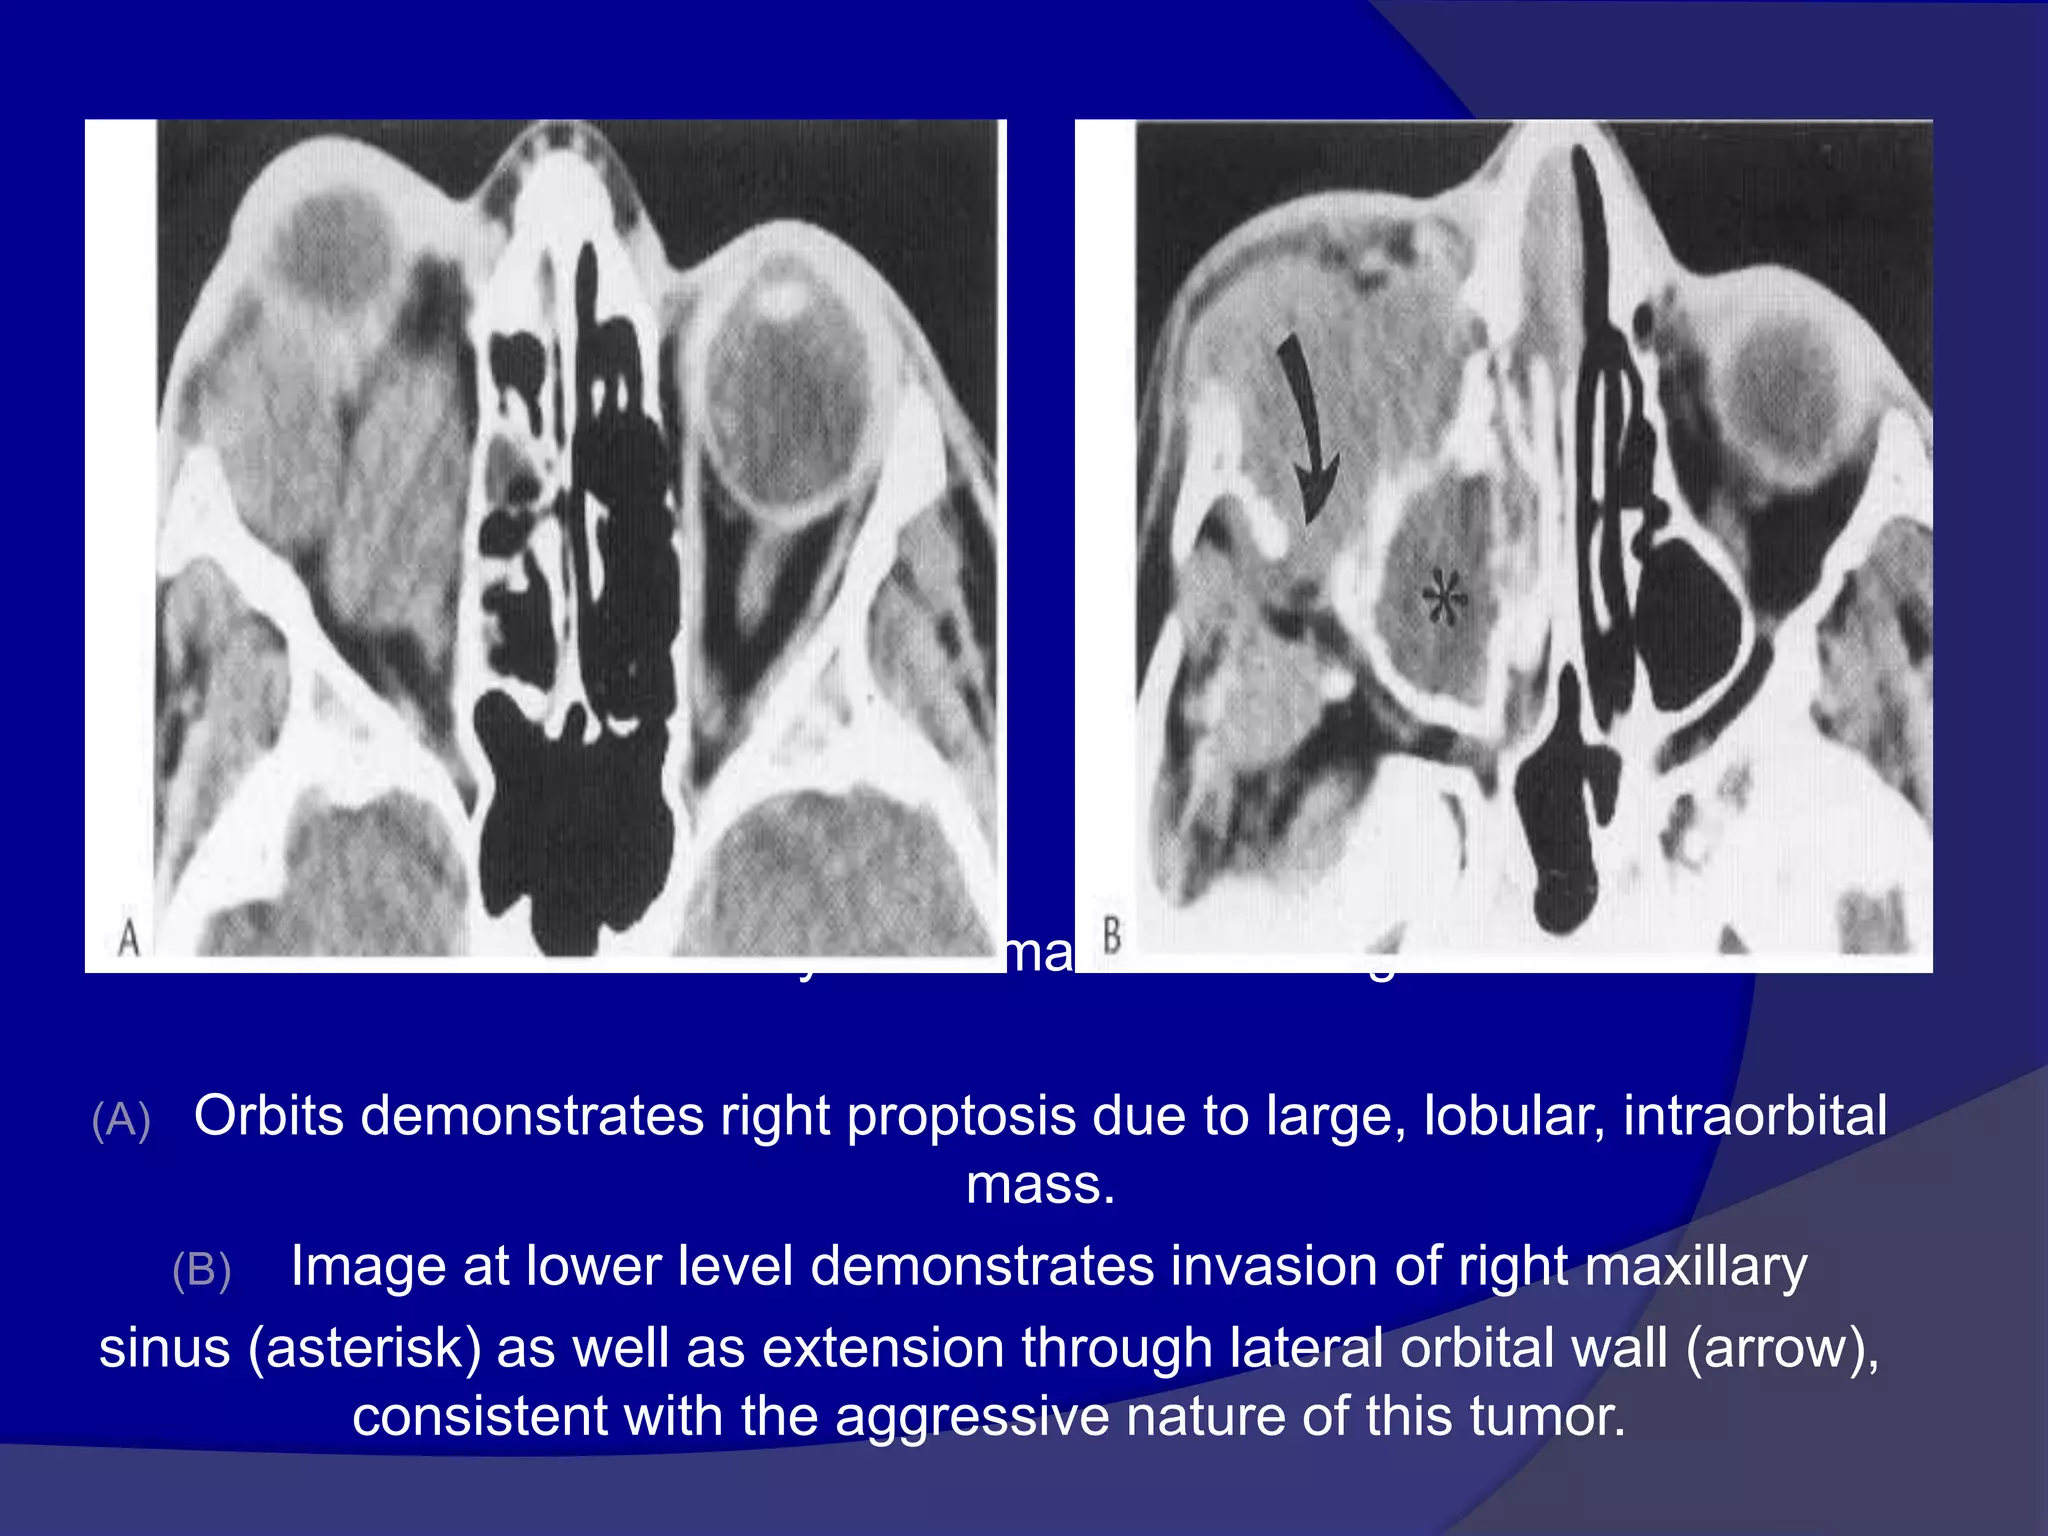

Rhabdomyosarcoma

• Rhabdomyosarcoma is the most common primary

orbital malignancy in the pediatric age group. with

most patients presenting below 6 years of age.

• Patients present with rapidly progressive

exophthalmos that may mimic orbital infection.

Spread of the tumor esp. intracranially, portends

poor prognosis.

• Imaging : Both CT and MRI will typically show a

mass involving an extra ocular muscle. Lesions

are isodense on CT and isointense on T1WI

when compared to muscle.

• There may be associated bony destruction and

contiguous extra orbital spread. The tumor

involves the globe less often. Marked

enhancement throughout the mass is seen after

contrast administration.

Rhabdomyosarcoma. CECT image

(A) Orbits demonstrates right proptosis due to large, lobular, intraorbital

mass.

(B) Image at lower level demonstrates invasion of right maxillary

sinus (asterisk) as well as extension through lateral orbital wall (arrow),

consistent with the aggressive nature of this tumor.